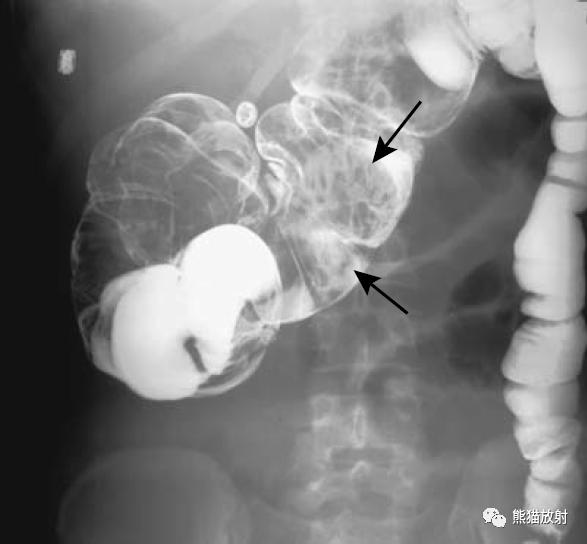

盲肠扭转。X线摄片显示中腹部肠管明显扩张(箭头)。钡餐检查示升结肠扭曲部位可见特征性的鸟嘴征(箭头)。

乙状结肠扭转。消化道造影侧视图可见乙状结肠局部走行扭曲(箭头)。